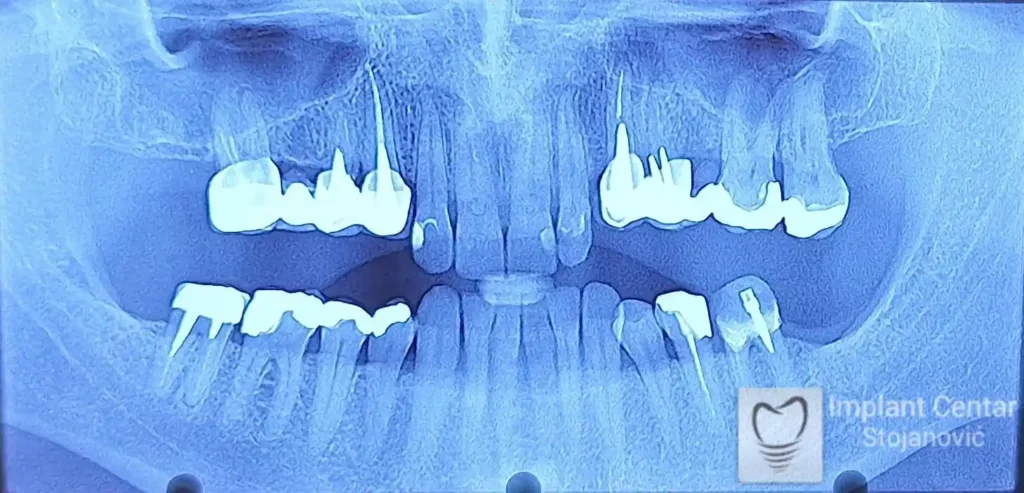

Na slici 1. i slici 2. prikazan je izgled pacijenta pre početka terapije – klinički i rendgenološki.

Nakon vađenja zuba, ugrađeni su implantati. Na slici 3 prikazan je ortopan snimak sa ugrđenim implantatima. Tokom perioda osteointegracije, pacijent je bio zbrinut fiksnim privremenim krunicama na implantatima, koje su izrađene samo dva dana nakon hirurške intervencije.